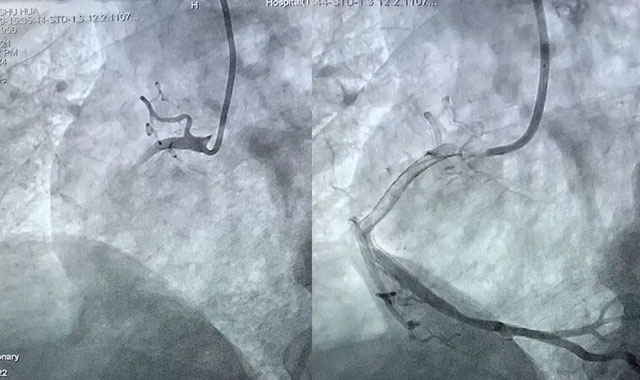

按照指导

基层医院快速完成规范处置

及时转诊患者

经介入治疗后,患者成功脱险

并转回基层医院康复治疗

罗钢教授牵头将CCU建设管理经验分享给基层医院,解决基层重症监护救治难题;赵立志教授助力基层成功完成首例房颤介入手术;江云东教授紧急驰援开展冠脉介入手术;潘洪教授讲授中医药诊治思路与辨证方法……

科室针对专科联盟单位设置5个专业组,由科室资深专家任组长,汇聚23名骨干,构建覆盖全心血管领域的技术指导梯队。依托复杂冠脉旋磨术、无导线起搏器植入术等10余项省内/川南领先核心技术,通过手把手带教、实操指导,推动房颤介入、冠脉造影等关键技术在基层落地生根,多家联盟医院相继实现专科技术“零突破”。